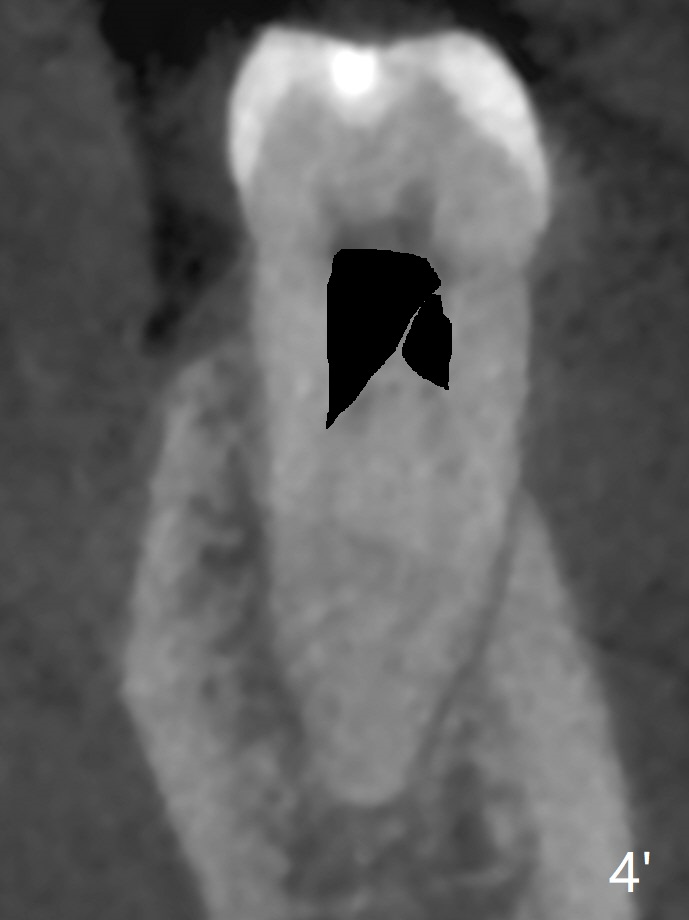

A 61-year-old man may have referral pain between #17 and 18. The canals at #18 are narrower than those at #17 (Fig.1-3). If #18 needs RCT, blocks should be removed (Fig.4-6 vs. 4'-6').